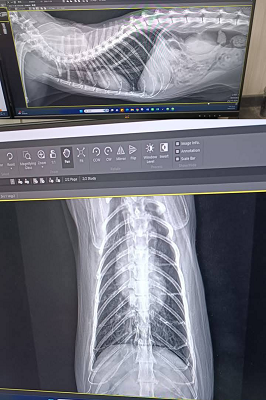

乖豹在安養之家受到良好照顧,身形越來越漂亮健美,看起來就是健康寶寶,但在2017年及2019、2020年間都突然出現無力站立、不願意走路、後肢肌肉看起來萎縮的情況,協會皆是安排乖豹至台大動物神經科專科看診,除了抽血檢驗、並將血液檢體送國外檢測重肌無力症、拍攝X光查看是否有腫瘤、核磁共振檢查及腦脊髓液採樣,查看是否腦脊髓發炎所造成的神經問題,但結果都沒有重肌無力症,也沒有找出確切原因,醫師懷疑可能是誤食含有有機磷的蟑螂藥,除了住院、吃類固醇、活性炭等用藥,照護員每天也數小時的為乖豹熱敷、按摩、復健,精神食慾有逐漸改善、走路慢慢恢復正常至痊癒,病癒後的乖豹又恢復平時的活潑調皮,在貓屋裡奔走玩耍。

原本是先讓乖豹再留在台北安養之家觀察一小段時間,希望確定健康無虞後,再讓他回到熟悉的大湖安養之家,但在2021年1月,照護員回報乖豹食慾體重都有漸降,1月23日呼吸看來急促,立刻約診沐恩醫院檢查,檢查結果,體溫40.3度,超音波及X光檢查發現胸腔有不明團塊及胸水,給予鎮定後抽出了有膿的胸水,當天辦理住院打泰寧抗生素針,醫師研判是嚴重的細菌感染和發炎造成膿胸,住院2天時,紅血球有持續降低的情況,血容比低到21,1月25日放置胸管引流、沖洗胸腔並引流膿水,每日都需要血檢及沖洗胸腔,在狀況嚴重會需要開胸手術移除胸腔中的膿包及清創,可能會需要輸血,幸好乖豹的食慾精神都有逐漸變好、血容比也有慢慢回升,至2月4日胸管沖洗出都已是乾淨的水,食慾精神也都穩定,醫師認為已可出院自行照護醫療,因治療剃掉肚子一大片毛的乖豹,讓大家很心疼,怕他冷為他穿上可愛又保暖的衣服,也每天準備好多好吃的罐罐幫他補身體,至2月17日回診的X光檢查,原本住院時胸腔有一大一小兩個團塊已經都不見了,這樣表示大團塊只是膿包,所以吃了抗生素就消失了,3月17日再回診,血檢結果都有很好的進步,體重也有回升,膿胸的危機已經解除,只要三個月後再回診拍X光及追蹤血檢即可。

原安置於苗栗貓屋的乖豹於2025年10月與其他貓咪全數移回台北安養之家後發現體型逐漸消瘦,且背上有一顆顆肉瘤以及牙齒有鬆動的狀況,於是安排2025年11月28日於沐恩看診,醫師表示整體狀況還不錯,背上粉瘤為良性,主要是牙結石嚴重,研判體重下滑應與此有關,需盡快安排牙周手術。後再於同年12月17日進行牙周手術,後面的臼齒、2顆下門牙及上顎那一顆不好犬齒都移除,保留下面兩顆犬齒,同時背部腫塊偏良性因此暫不切除。本筆醫助是自2025年11月28日至2025年12月17日間於沐恩醫院的費用,包含看診各項檢驗、牙周手術及用藥。